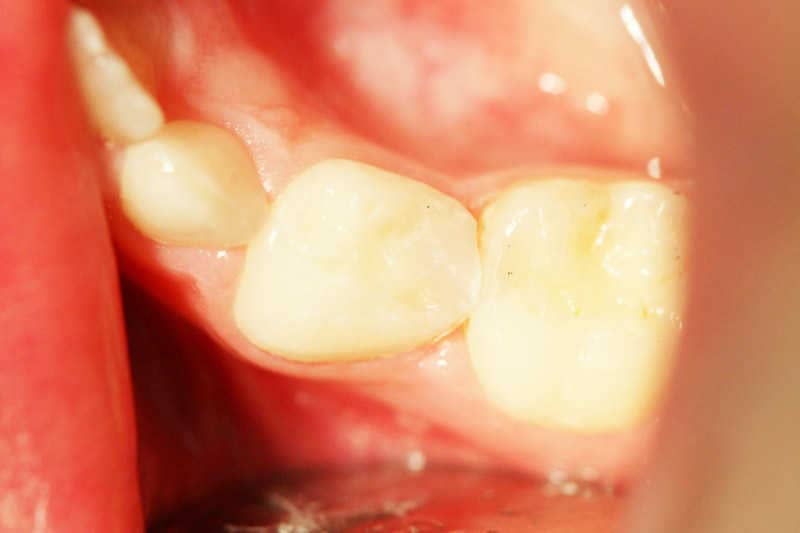

A bal alsó 4-es tejfog a tömés után

A bal alsó 4 es tejfog a tömés után